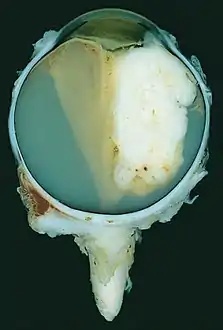

| A pathology specimen of a retinoblastoma tumor from an enucleated eye of a 3-year-old female | |

Morphology

Gross and microscopic appearances of retinoblastoma are identical in both hereditary and sporadic types. Macroscopically, viable tumor cells are found near blood vessels, while zones of necrosis are found in relatively avascular areas. Microscopically, both undifferentiated and differentiated elements may be present. Undifferentiated elements appear as collections of small, round cells with hyperchromatic nuclei; differentiated elements include Flexner-Wintersteiner rosettes, Homer Wright rosettes,[29] and fleurettes from photoreceptor differentiation.[30]